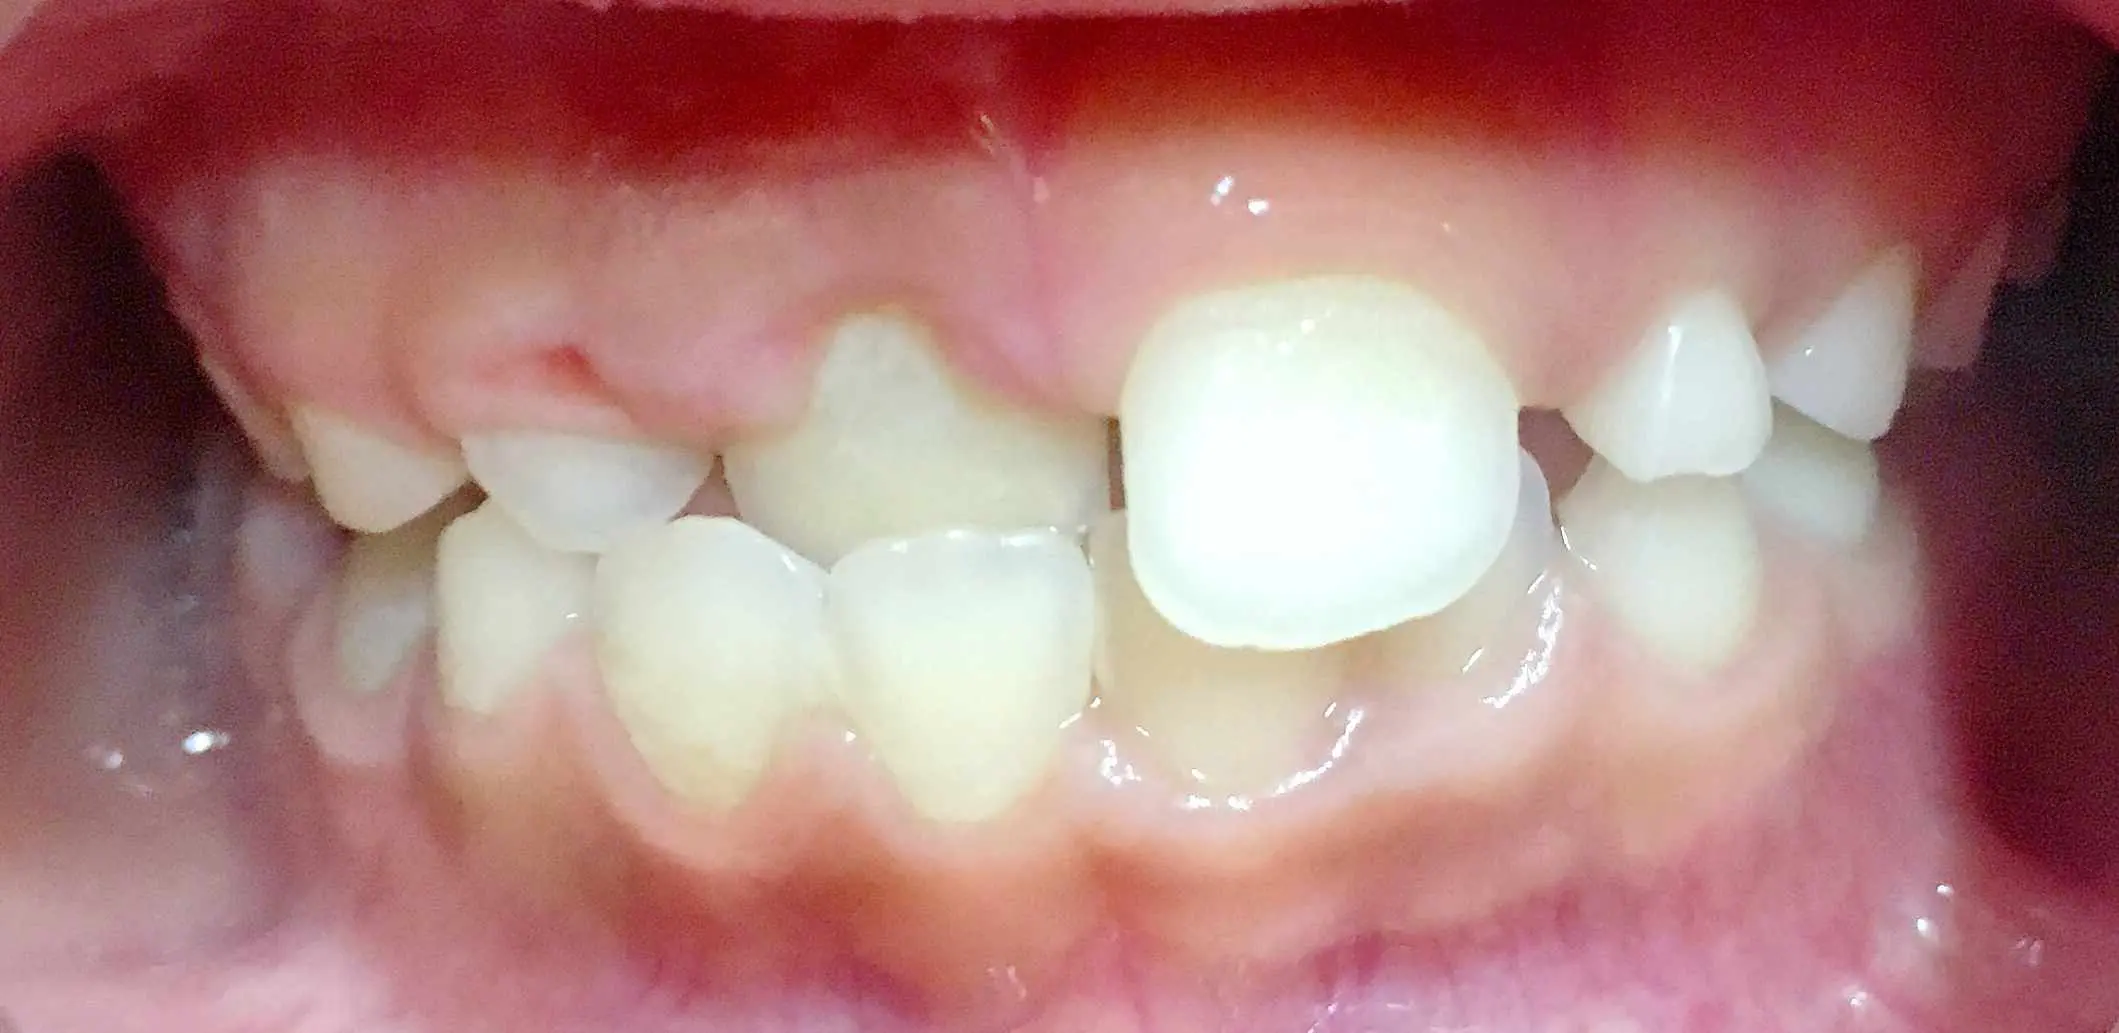

Crossbite

November 10, 2025 A simple removable appliance is better than clear aligners for crossbite correction! Read more